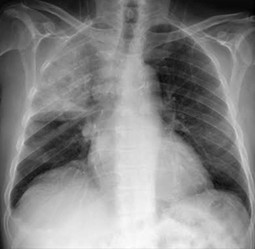

Q184. What is the most appropriate diagnosis for the image below?

- Collapse of the right upper lobe

- Consolidation of the right upper lobe

- Right lung abscess

- Right upper lobe bronchogenic carcinoma

Answer: A